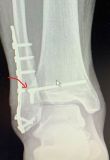

4. Metal work in lateral malleolus with the syndesmotic screw to be broken in a 30-year-old male.

Treatment: Removal all the implant work plus the syndesmotic screw with specific technique.

The lag screw did not remove I. Ten months down the line of the procedure, anteroposterior x-ray ankle shows the broken screw II. During the procedure a specific technique is using to remove the major part of the broken screw III. Anteroposterior view during the procedure is showing that the broken screw has been removed